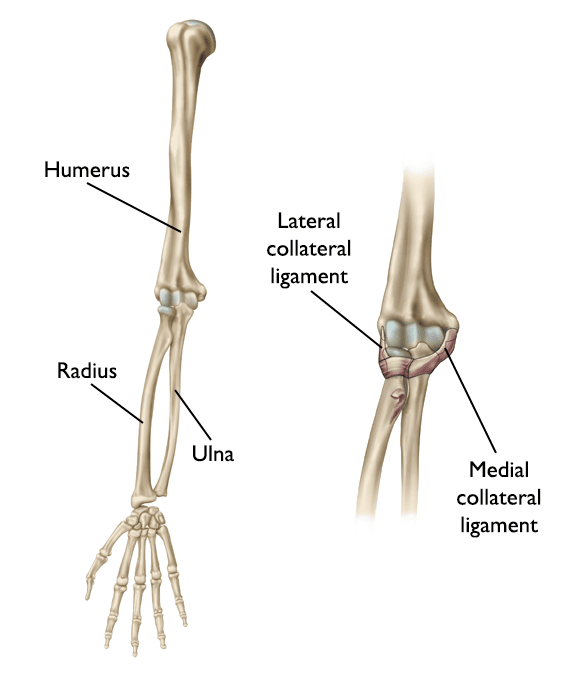

Three bones come together to make up the elbow joint.

• The humerus  is the bone in the upper arm.

• Two bones in the forearm, the radius and the ulna, form the lower part of the elbow.

Each of these bones has a very distinct shape.

Ligaments connected to the bones keep the elbow joint together and the bones in proper alignment.

Elbow anatomy

(Left) The bones of the elbow and forearm shown with the palm facing forward. (Right) The ligaments of the elbow.

Reproduced with permission from J Bernstein, ed: Musculoskeletal Medicine. Rosemont, IL, American Academy of Orthopaedic Surgeons, 2003.